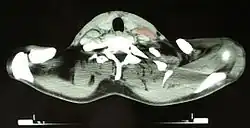

КТ изображение пациента 46 лет с лимфомой Ходжкина, снимок на уровне шеи. На правой стороне шеи пациента визуализируются увеличенные лимфатические узлы (отмечены красным).

Основным критерием для постановки диагноза служит обнаружение гигантских клеток Рид — Березовского — Штернберга и/или клеток Ходжкина в биоптате, извлечённом из лимфатических узлов. Используются и современные медицинские методы: (ультразвуковое исследование органов брюшной полости, компьютерная рентгеновская или магнитно-резонансная томография органов грудной клетки). При выявлении изменений в лимфатических узлах необходима гистологическая верификация диагноза.